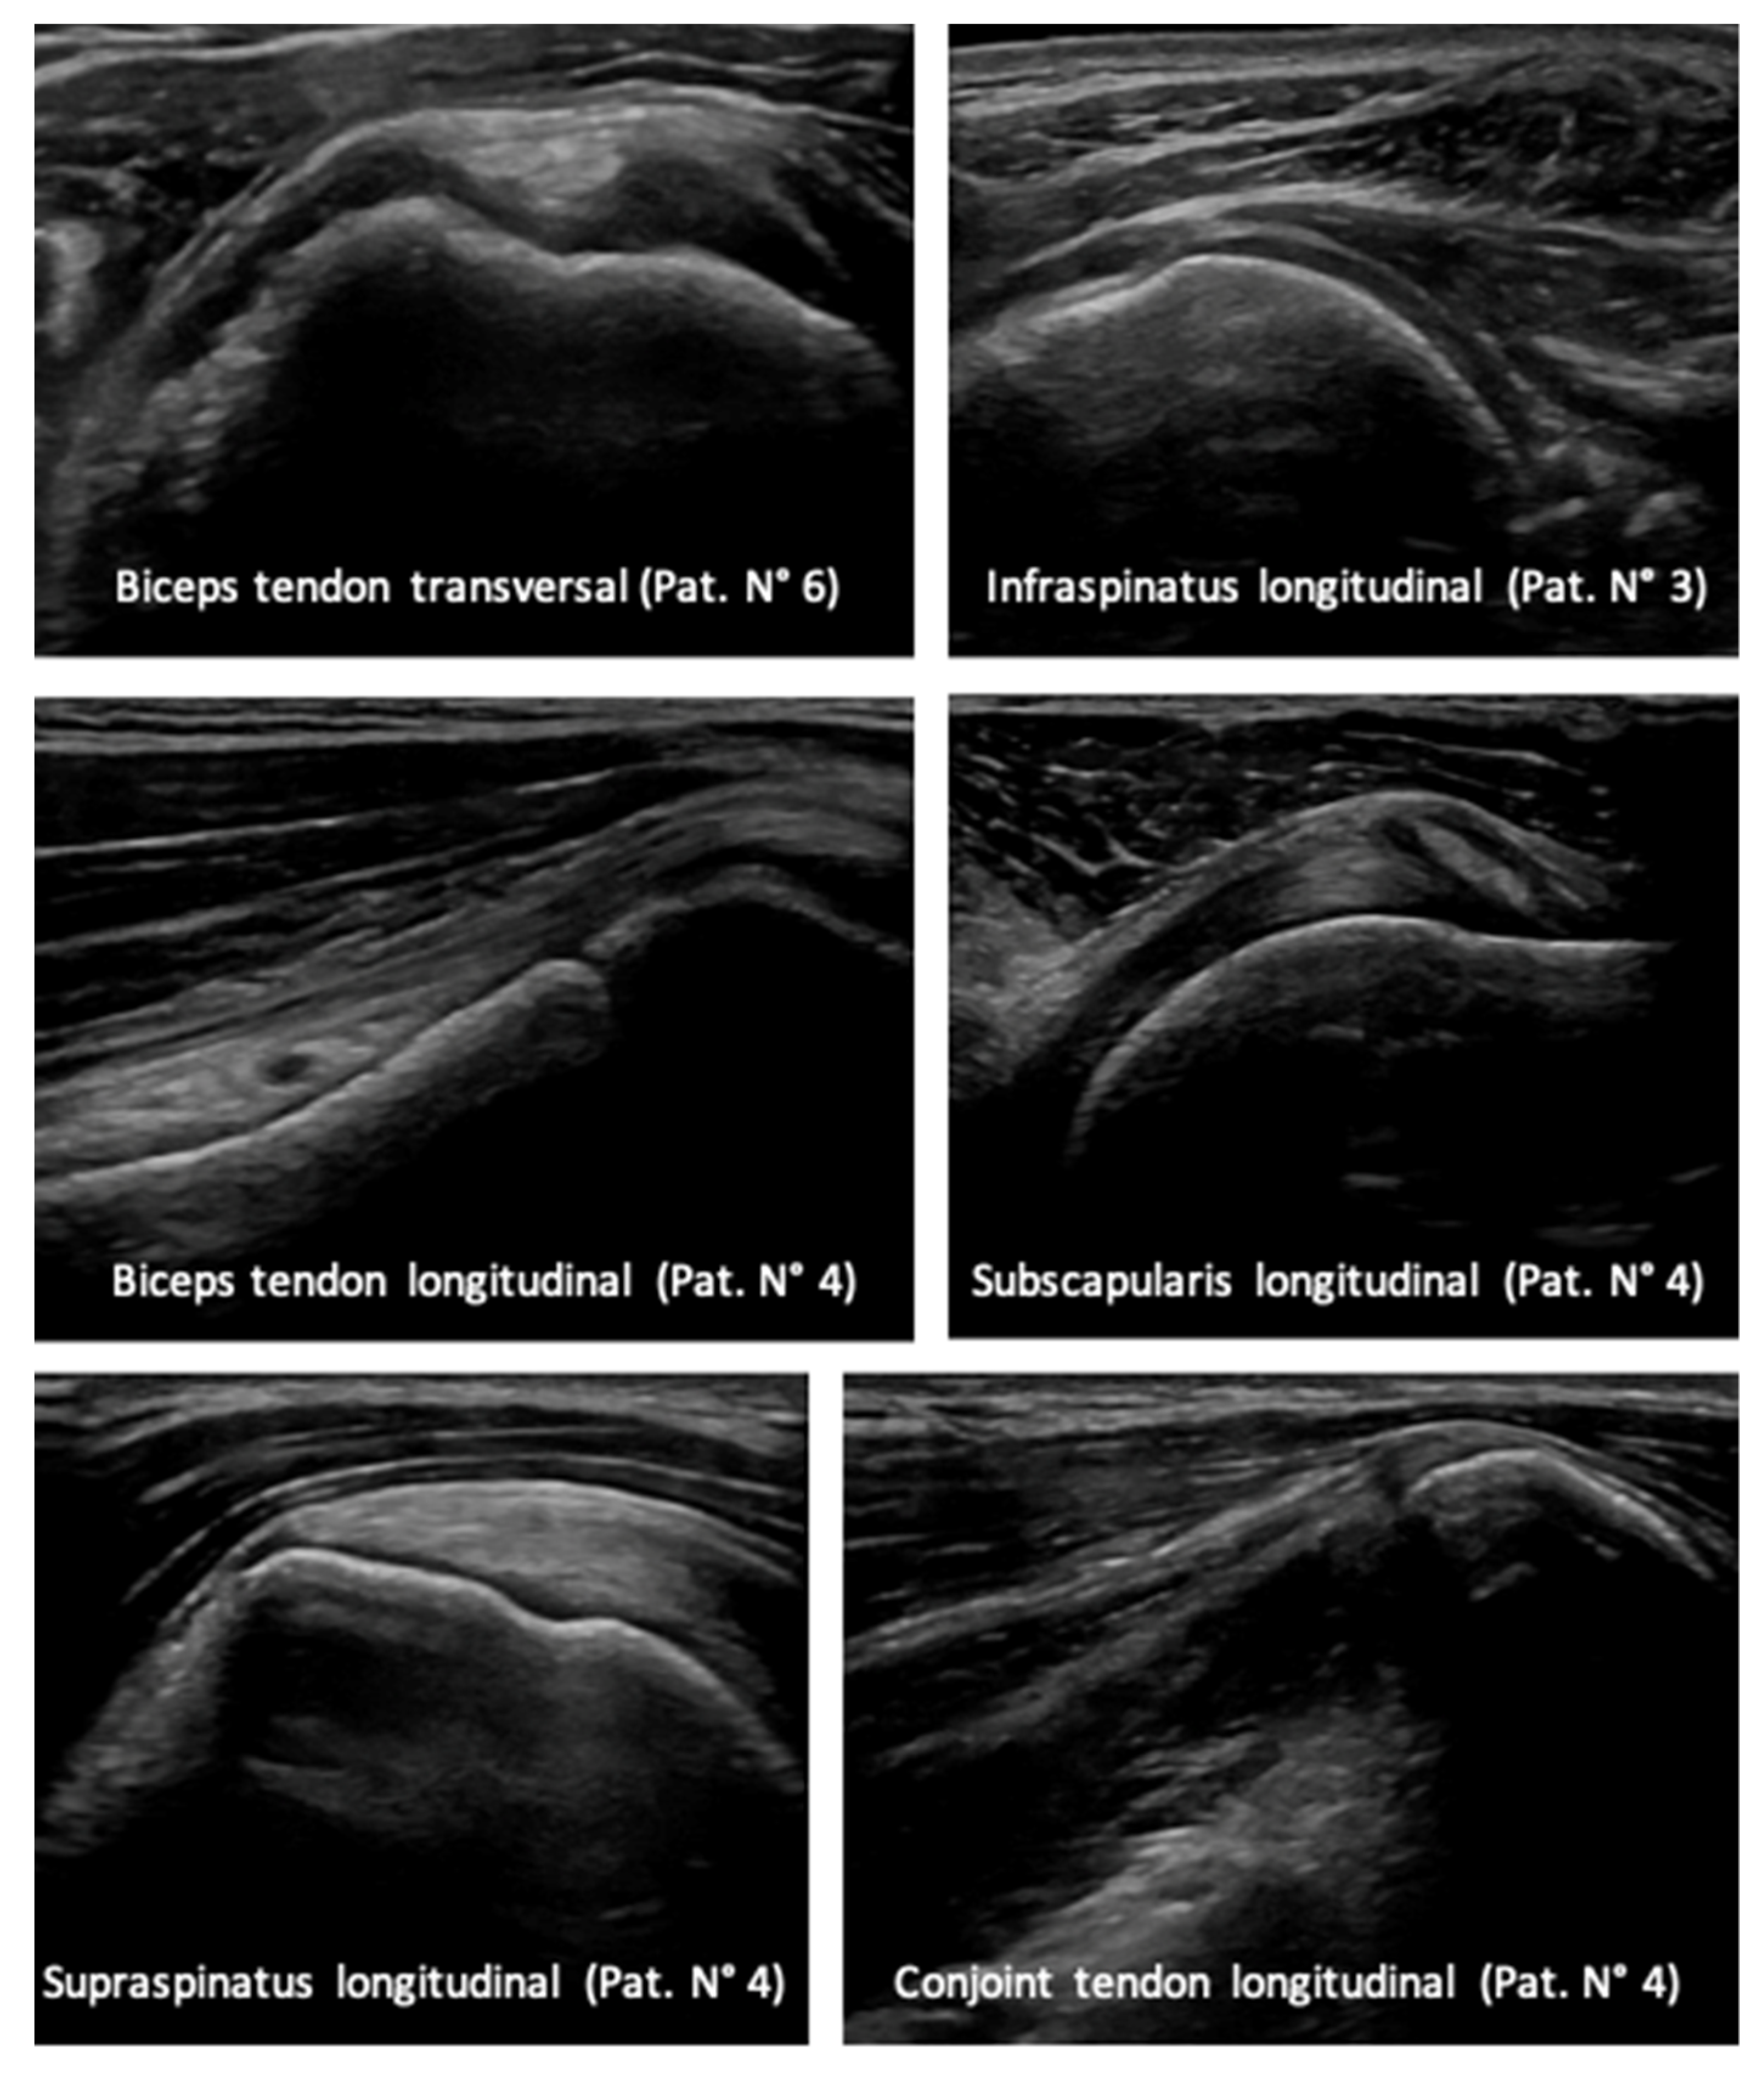

2.3. Ultrasound Imaging

All patients were scanned in a sitting position with a relaxed arm hanging freely on the side. For the examination, a GE LOGIQ E9 ultrasound system (GE Healthcare; Chicago, IL, USA) with a linear transducer with a bandwidth of 6–15 MHz was used.

The tendons of the subscapularis, supraspinatus and infraspinatus tendon were examined along their long and short axis.

The subscapularis tendon was examined with the arm externally rotated and the elbow fixed at the iliac crest. For the evaluation of the supraspinatus tendon, the patient’s arm was placed posteriorly, with the palmar side of the hand on the superior aspect of the iliac wing with the elbow flexed and directed posteriorly. To examine the infraspinatus tendon, the arm was placed anteriorly with the hand on the opposite shoulder.

The long head of the biceps tendon was examined along the long and short axis with the arm placed in slight internal rotation. The integrity of the conjoint tendon was examined also in both planes with the arm placed in external rotation.

A sonographic examination of the shoulder two years postoperatively showed normal rotator cuff, long head of biceps and conjoint tendon (

Figure 4).